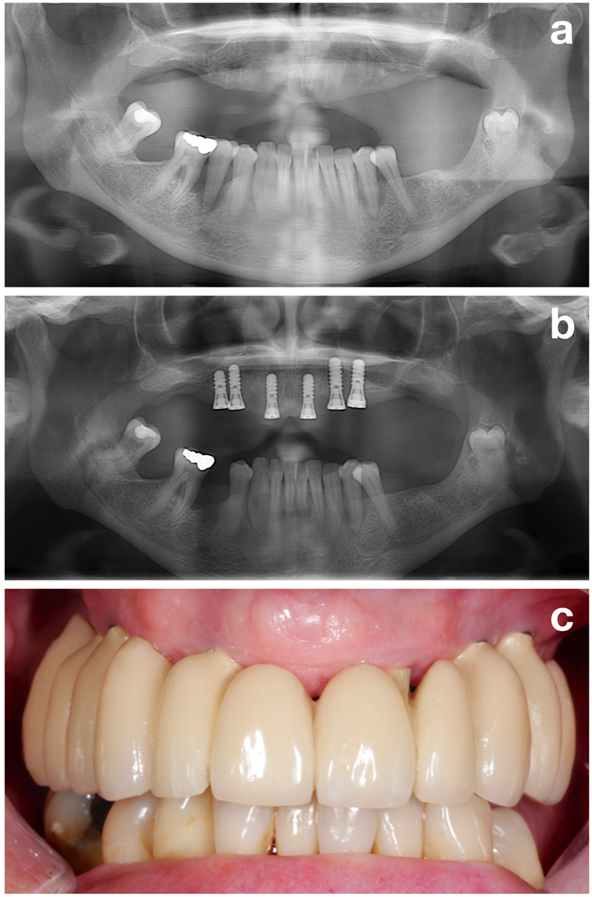

Figura 2. Prima dell'inserimento dell'impianto è necessario che la situazione parodontale sia stabile. Paziente prima del trattamento parodontale (a), dopo il trattamento parodontale e l'installazione dell'impianto (b) e dopo la ricostruzione con protesi (c). © Dott.ssa K. Bertl

La prima parte (ossia, la fase di pre-trattamento) mira a preparare perfettamente il paziente per l'effettivo inserimento dell'impianto valutando tutti i potenziali fattori di rischio ma focalizzandosi su uno dei più importanti: l'ottenimento di una situazione parodontale stabile (Figura 2).